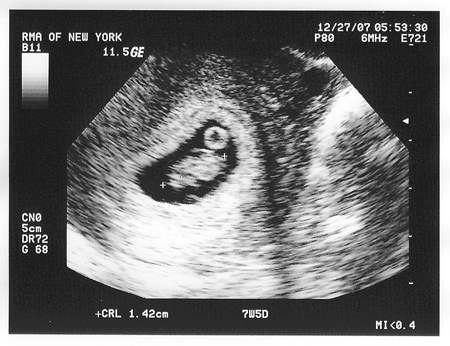

Фото малюка, УЗД

Сьомий тиждень вагітності - вдалий час для того, щоб стати на облік. Чим раніше ви це зробите, тим раніше пройдете необхідне обстеження і будете впевнені, що все в порядку. Вам будуть призначені аналізи крові, сечі, вимірювання артеріального тиску, росту, ваги і т.д. При необхідності лікар може призначити дослідження рівня гормонів крові, наприклад, ХГЧ на 7 тижні вагітності. Також вам випишуть направлення на ультразвукове дослідження. УЗД на 7 тижні вагітності проводиться тільки за показаннями, а скринінгове дослідження призначається на 11-14 тиждень.

Чому 7 акушерська тиждень вагітності відрізняється від гестаційної? Фактичним початком вагітності є день овуляції, коли відбулося запліднення яйцеклітини. Однак це у різних жінок відбувається в різні дні менструального циклу, тому справжнє початок вагітності визначити вкрай складно. Тому для зручності підрахунків і точності термін вагітності прийнято вважати від першого дня останньої менструації. Тому гестаційний термін відрізняється від акушерського приблизно на два тижні. Однак загальноприйнята саме акушерська система відліку, і завжди термін вагітності, нормативи розмірів малюка вказуються саме за цією системою. Дуже хочеться вже зробити УЗД і побачити малюка! Чи можна зробити фото плода під час УЗД?

Ультразвукове дослідження - це безпечна для плоду і матері діагностична методика, і вже в 7 тижнів цілком можна зробити УЗД. Однак на такому ранньому терміні малюк ще дуже маленький, тому фото, на якому помітні риси обличчя, положення, ручки, ніжки малюка, зробити ще не вийде. Перше УЗД призначається на 11-14 тиждень вагітності. На цьому терміні вже можна виключити аномалії розвитку, генетичну патологію малюка, а на фото при УЗД буде все добре видно. Тому краще трохи почекати. Що робити, якщо болить живіт на 7 тижні вагітності?